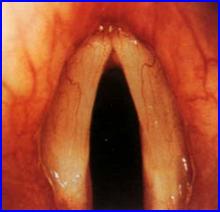

正常聲帶喉癌2.聲門上癌 生長於喉室、室帶、會厭,也包括杓狀軟骨及杓會厭皺襞的腫瘤。

2、聲門型局限於聲帶的癌腫,以前、中1/3處較多,分化較好,屬Ⅰ、Ⅱ級。發展較慢,由於聲帶淋巴管較少,不易向頸淋巴結轉移。主要症狀為聲嘶,逐漸加重。腫瘤增大時,阻塞聲門,可出現喉喘和呼吸困難,晚期有血痰和喉阻塞症。